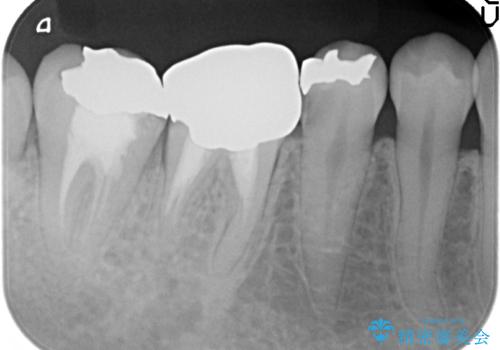

- 右下5番目の歯がしみるといらっしゃった方の症例です。

銀歯及び虫歯を除去し、適合に優れたPGA(ゴールド)インレーにて修復を行いました。

虫歯治療は虫歯の進行度によって処置が変わってきます。

虫歯が小さければ、インレー・クラウン等による修復・補綴処置を行うだけで済みます。

しかし虫歯が大きくなると神経処置や抜歯等をしなければならない場合もあります。